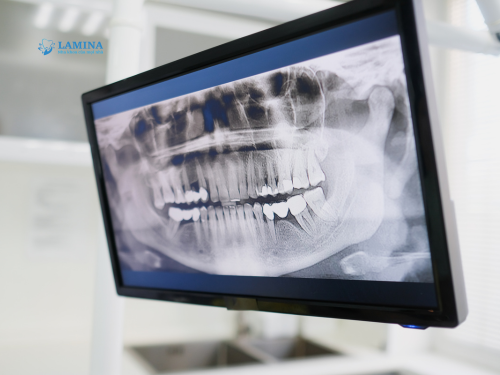

Phim được hiển thị ngay trên màn hình máy tính.

Công nghệ x quang kỹ thuật số hiện nay giúp giảm đến 90% lượng tia so với máy cũ, hoàn toàn an toàn cho người chụp.

Tại Nha khoa Lamina, tất cả phòng chụp đều dùng máy ConeBeam CT 3D thế hệ mới, cho hình ảnh rõ nét, chi tiết từng cấu trúc xương và răng, hỗ trợ bác sĩ chẩn đoán chính xác hơn.